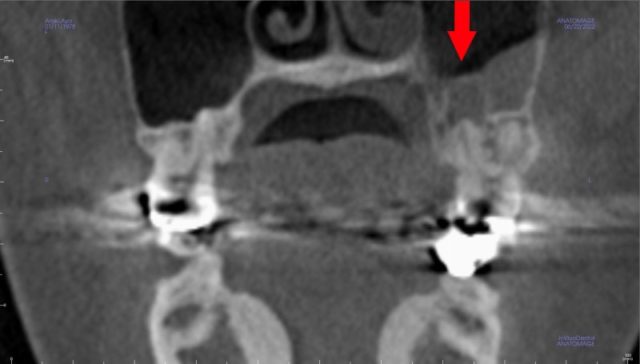

顔も頬骨も痛い 急性歯性上顎洞炎が、

起こる前の状態です。

上は、初診時の左 慢性上顎洞炎です。

粘膜が厚くなっている(粘膜の肥厚)

がありますが、無症状です。

頬骨 痛いとき 急性上顎洞炎の治療

慢性上顎洞炎が、突然、急性化し、

顔が痛いし、頬骨も痛いほどの

急性上顎洞炎がおきました。

緑矢印 正常な上顎洞

黄矢印 膿がたまっている上顎洞

赤矢印 原因になった歯根

(上顎洞の底の骨が、溶けています)